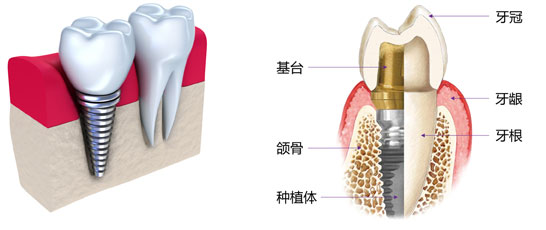

种植体(人工牙根)为特殊的材料(纯钛或者钛合金)制成,其生物相容性最好,与人体没有排异,可以与牙槽骨组织紧密结合、坚固耐用。

而种植体的外形、螺纹的设计及基台的匹配都是经过长期科学研究及临床测试逐步演变而来的,且因其体积小,对制作工艺的要求及其精确、严格。